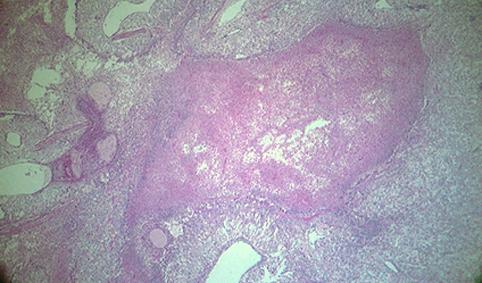

질환(병리주체)의 분류 전이성종양/

부위(장기별) 소장/공장

검사방법 마이크로

종양의 최대경(밀리미터) 40이상